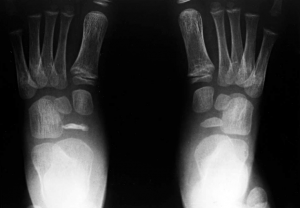

La visita presso uno specialista e la storia clinica del paziente devono essere completate da una radiografia.

La radiografia mette in evidenza l’appiattimento dello scafoide che appare inoltre sclerotico e frammentato; è sempre consigliabile eseguire anche un controllo radiografico dell’altro piede.

Nella fase iniziale la radiografia della testa metatarsale non mostra evidenti cambiamenti.

Radiografie successive rendono invece evidenti la deformazione, lo slargamento, l’appiattimento, l’addensamento e la frammentazione di quest’ultima.